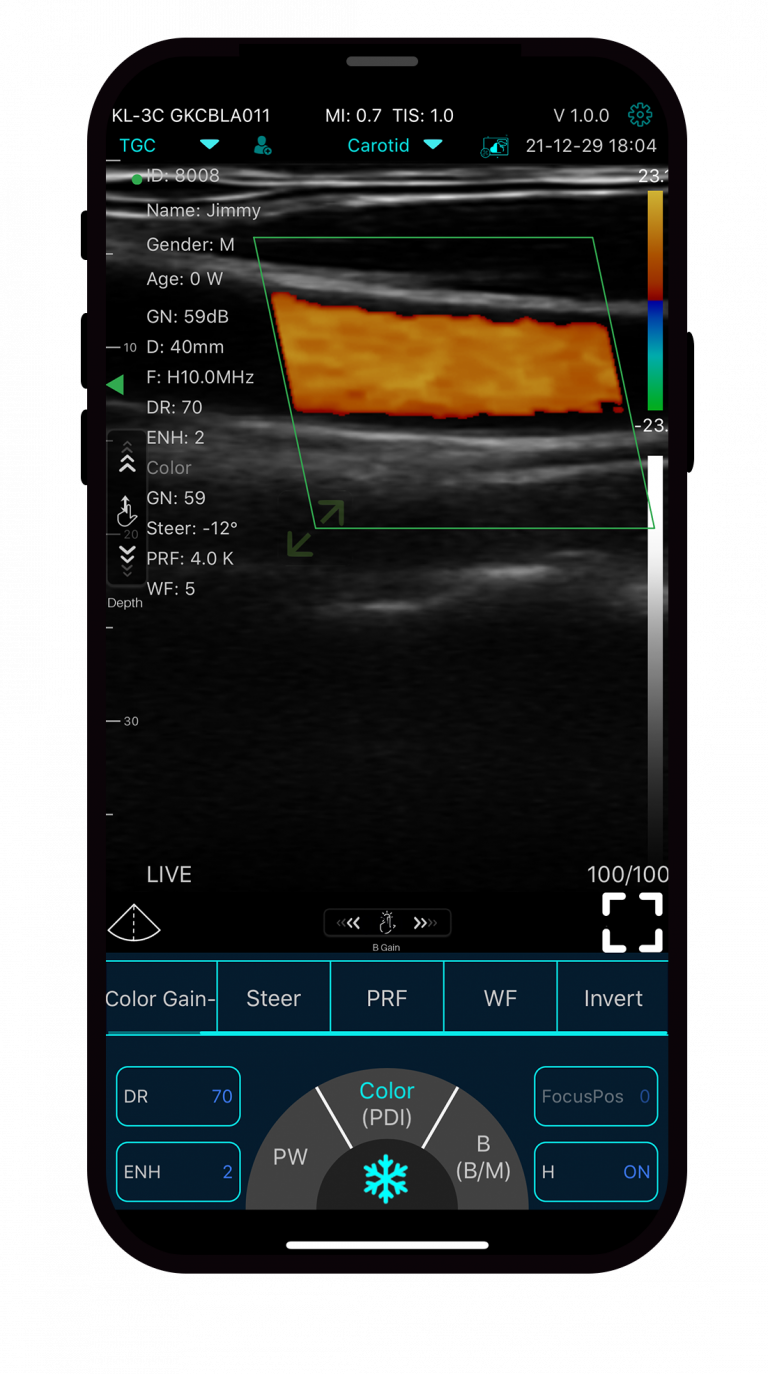

myMIDES C10 ultrazvučna sonda s dvije glave

myMIDES C10 je idealna ultrazvučna sonda za brze i precizne ultrazvučne preglede u mnogim područjima primjene.

S mobilnom dvoglavom sondom ultrazvučne slike visoke rezolucije mogu se jednostavno prenijeti na – tablet, – prijenosno računalo, – pametni telefon putem WLAN veze.

- Načini rada: B / B+B / B+M / Color / PW / PDI / B+Color+PW

- Linearni i konveksni pretvarač u jednoj sondi

- Kompatibilan sa sustavima Android, IOS, Windows

U praksi i u pokretu: myMIDES C10 je uvijek spreman za upotrebu!

myMIDES C10 je najnovije sonografsko rješenje specijalista za ultrazvuk MIDES, koji s više od 25 godina iskustva u medicinskoj tehnologiji pouzdano nudi najvišu kvalitetu i najbolju uslugu.

Načini rada zaslona: B / B+B / B+M / Color / PW / PDI / B+Color+PW

linearna glava:

- Frekvencija: 7,5-10,0MHz

- Dubina: 20-100 mm

konveksna glava:

- Frekvencija: 3.2-5.0MHz

- Dubina: 90 – 305 mm

Područja primjene:

- abdomen

- strukture blizu površine

- MSK (mišićno-koštani)

- kardiologija

- ginekologija

- urologija

- bubreg

- pluća

- grudi

- štitnjača

- pedijatrije

- karotida